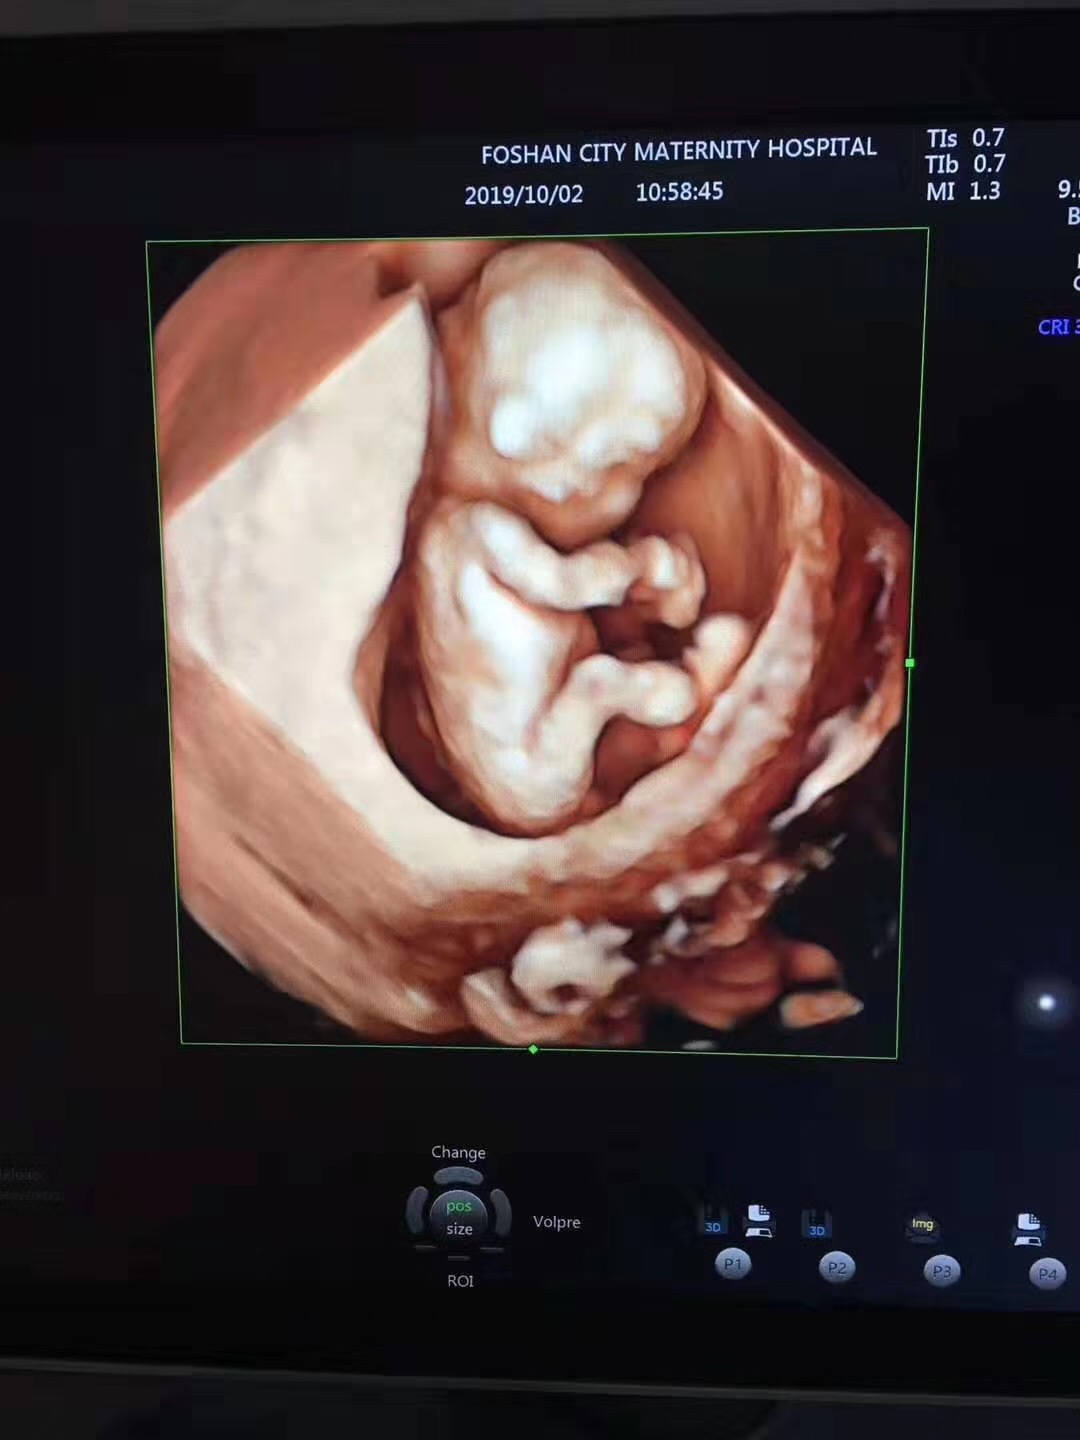

三、四维大排畸

做这项检查时候可以多角度观察到宝宝的发育情况,比如胎儿的器官发育,手脚脊柱发育是否出现了畸形,当然毕竟医学手段还有一定的局限性,四维彩超也并不是什么畸形都能检查出来,比如胎儿的眼睛听力就无法得知,还有一些先天性的疾病也无法得知。